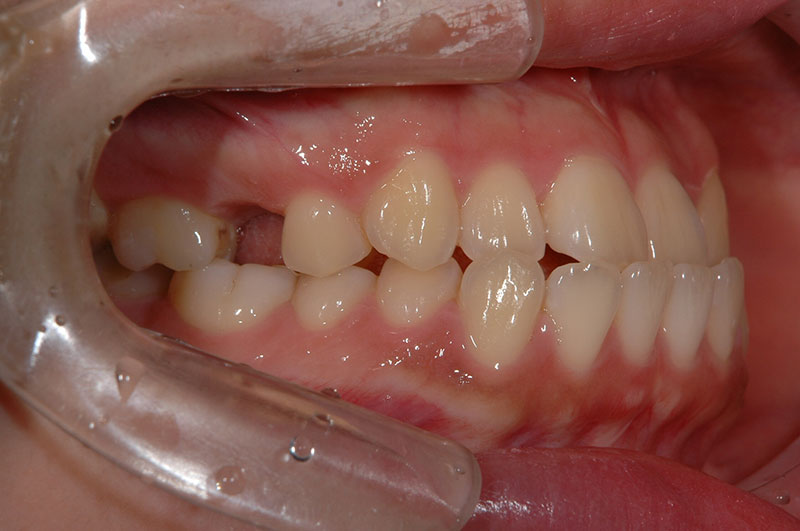

今回は反対咬合に対して、外科手術を行わずに矯正治療のみで改善した成人の症例をご紹介します。

「反対咬合=手術が必要」と思われがちですが、噛み合わせの状態によっては、今回のように矯正治療だけで改善が可能なケースもあります。

治療前後の変化を実際の症例写真でご覧いただくことで、

反対咬合がどのように改善するのかを、イメージしていただければと思います。

症例の概要(手術なし・成人の反対咬合)

術前

術後

| 主訴 | 反対咬合 |

| 初診時年齢 | 24歳 |

| 治療内容・使用した装置 | 頬側ブラケットを用いた永久歯全体の矯正治療、アンカースクリュー |

| 抜歯の有無 | 左右下顎第一小臼歯、左側上顎第二小臼歯抜歯 |

| 治療期間 | 約24ヶ月 |

| 費用 | 総額819,500円(税込) (相談料、検査料、診断料、動的治療費、抜歯費、アンカースクリュー埋入、除去費、保定期間料等含む) |

| 治療に伴うリスク・副作用 | 歯の移動に伴う痛み、上下顎前部の歯根吸収、装置による口内炎、ブラッシング不良によるむし歯、歯周炎 |